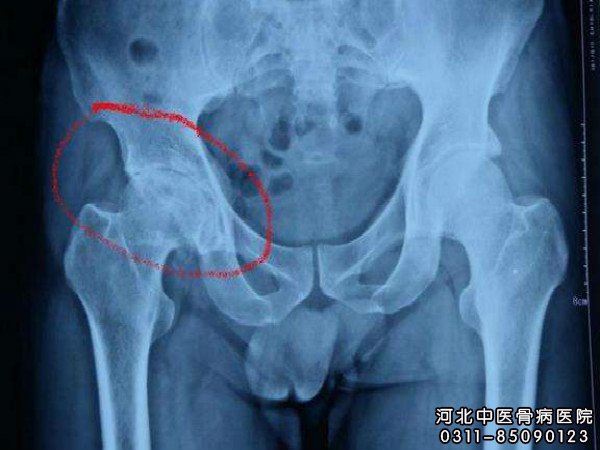

患者如何远离股骨头坏死并发症?严重双侧的老年患者,或者股骨头坏死术后需要长时间卧床的患者,出现并发症的几率较高,应做好防护措施。那么,患者如何远离并发症?

患者如何远离股骨头坏死并发症?河北中医骨病医院骨病专家谢主任介绍: